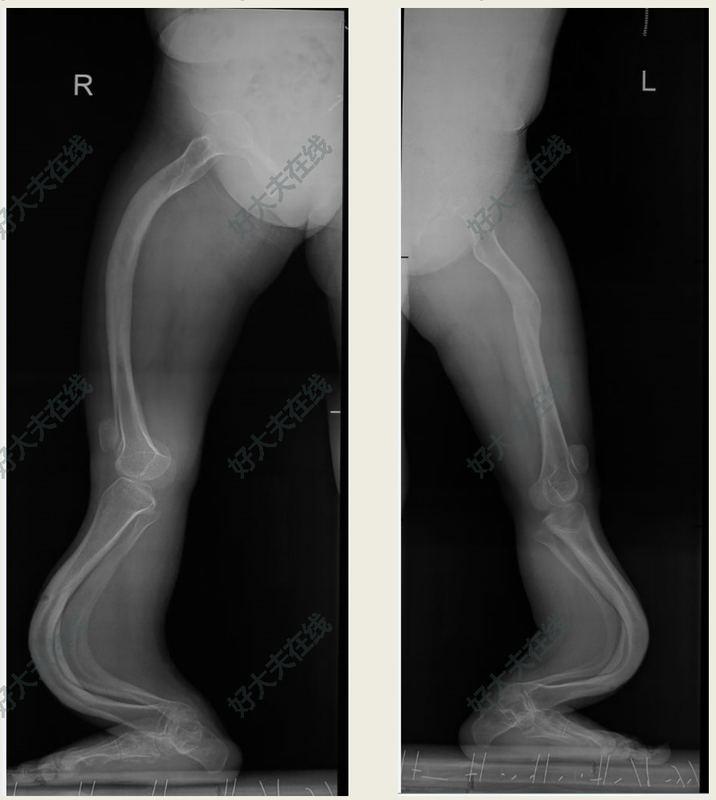

治療前成人成骨不全癥患者骨骼畸形矯正困難,軟組織攣縮嚴重,骨骼發(fā)育差,髓腔封閉。截骨后愈合困難。聯(lián)合外固定支架分期手術可以有效的解決這一難題治療中先利用外固定支架矯正攣縮的畸形然后再進行髓內固定手術治療后治療后3年畸形獲得糾正,恢復正常行走功能